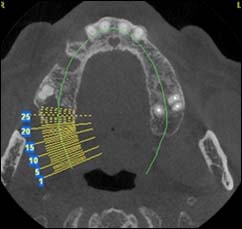

Coupe axiale